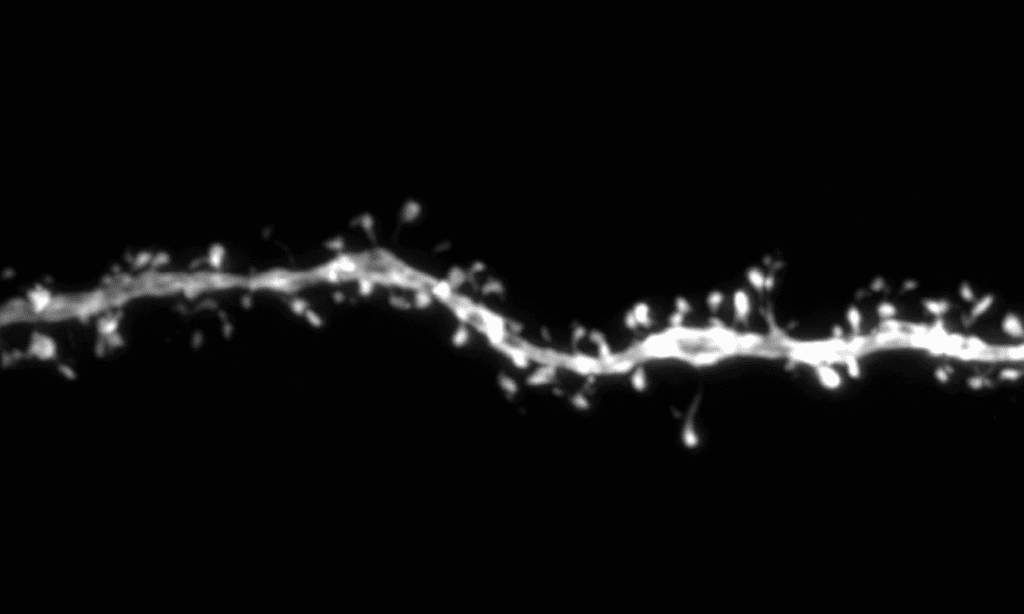

To address this, Dr. Baptiste Libé-Philippot, a Postdoctoral Fellow in the Vanderhaeghen lab, switched off SRGA2B and SRGAP2C in human neurons, transplanted them into mouse brains, and carefully monitored synapse development over an 18-month period.

‘We discovered that when you turn off these genes in human neurons, synaptic development speeds up at remarkable levels’, says Dr. Libé-Philippot. ‘By 18 months, the synapses are comparable to what we would expect to see in children between five and ten years old! This mirrors the accelerated synapse development observed in certain forms of autism spectrum disorder’.